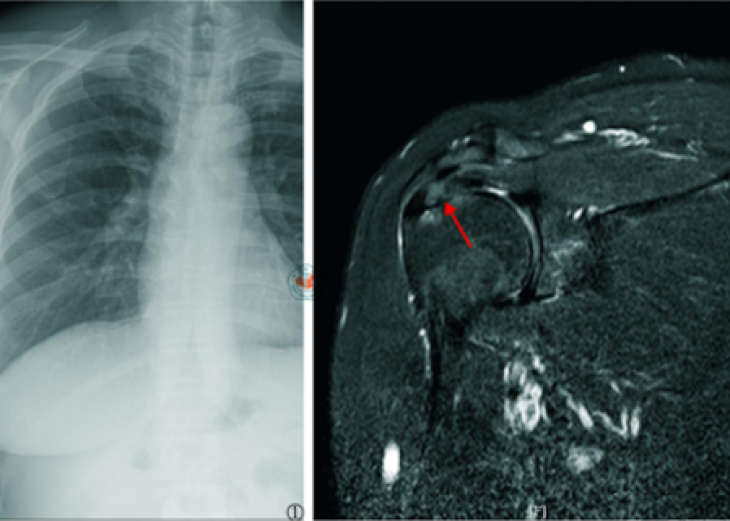

肩袖钙化性肌腱炎是常见的引起肩关节剧痛的疾病之一,好发年龄为30~50岁,女性稍多于男性。当肩袖钙化性肌腱炎处于急性发作期时,患者常常出现肩部剧烈疼痛,夜不能眠,严重影响正常的工作和生...